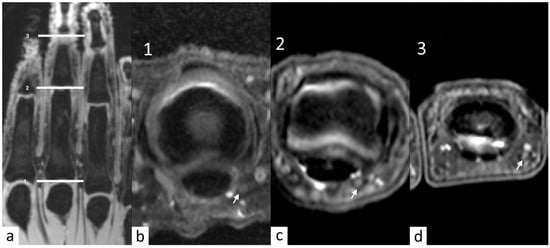

3. Results

3.1. Quality Assurance

3.2. Nerve Description

3.3. Pacini Description